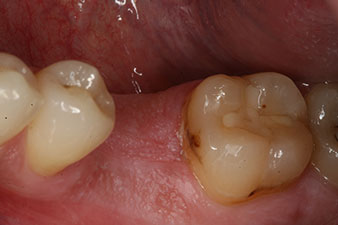

Abb. 1: Klinische Ausgangslage nach Abheilung der Extraktionsalveole 36: Die Knochenbasis ist breit und es ist genügend keratinisierte Gingiva vorhanden.

Bei einem 28-jährigen Patienten mit ausgeprägter Raucheranamnese musste Zahn 36 als Folge einer rezidivierenden apikalen Parodontitis extrahiert werden.

Wegen der weitgehend intakten Nachbarzähne kam als Lückenversorgung nur ein Implantat in Frage.